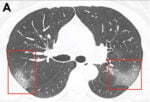

Best Alternatives To CT Scan; After AIIMS Chief Warns Of Cancer Risk

CT imaging of COVID